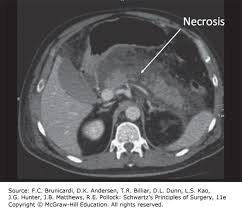

• Investigații imagistice – de exemplu, ecografie sau tomografie computerizată – pentru a observa structura pancreasului și a organelor din vecinătate;